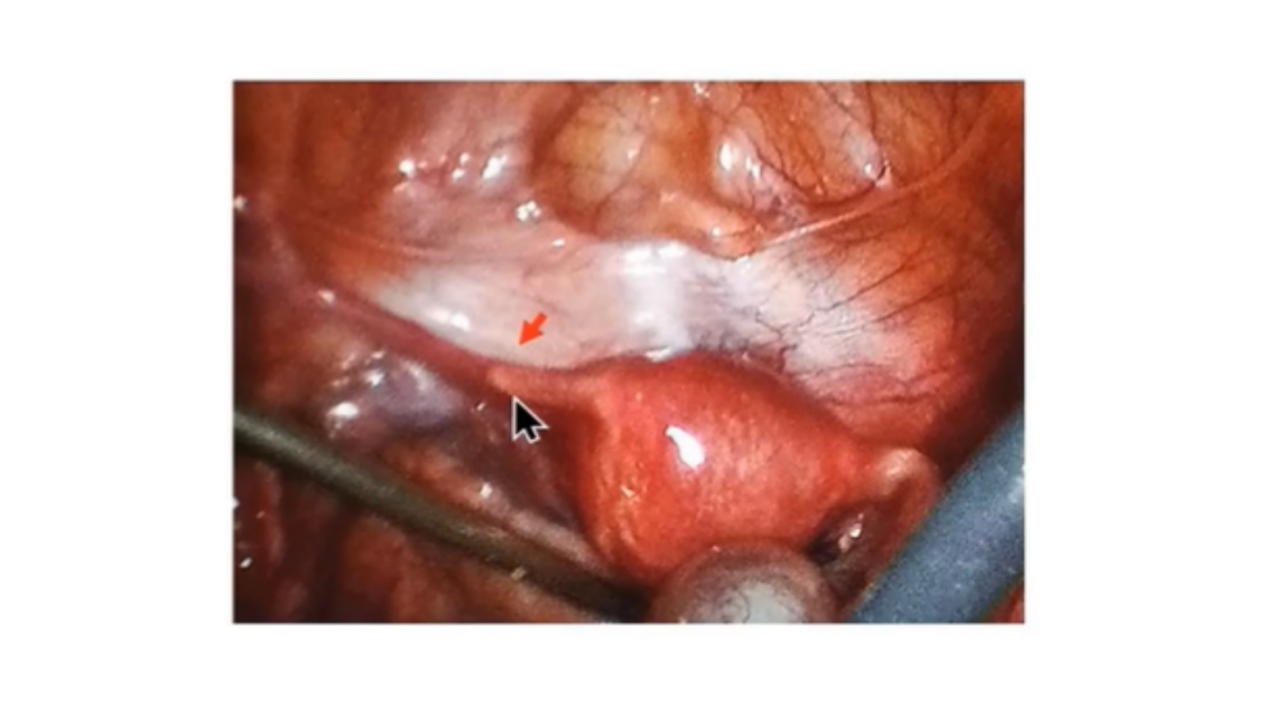

腹腔镜显示左侧圆韧带和正常子宫,未见左侧输卵管、卵巢,只有2厘米的输卵管残余(箭头处)。右输卵管和右卵巢(含黄体)正常。

左侧输卵管突然中断并左侧卵巢缺失。